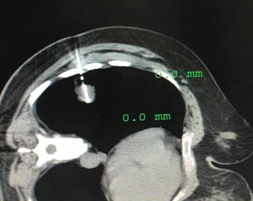

肺部CT专指影像学名词——不同于毛玻璃样改变,指肺部非特异性局灶性小结节样密度增高影。

分为:单纯型(略高密度,均质)、混合型(成分密度不一致,含有实性成分)

病理类型:良性(炎症、结核、纤维化、不典型腺瘤样增生),恶性(早期肺癌, 占检出的5%~10%)。

1 肺磨玻璃样病变的特征

发展非常缓慢,以年计算——发现了也别慌

发展结局多种多样——大多数不是癌

处理策略没有共识——不同医生意见不一致

小磨玻璃样结节恶变风险很低(<5mm, 0.9%)

恶性磨玻璃样结节治疗预后良好